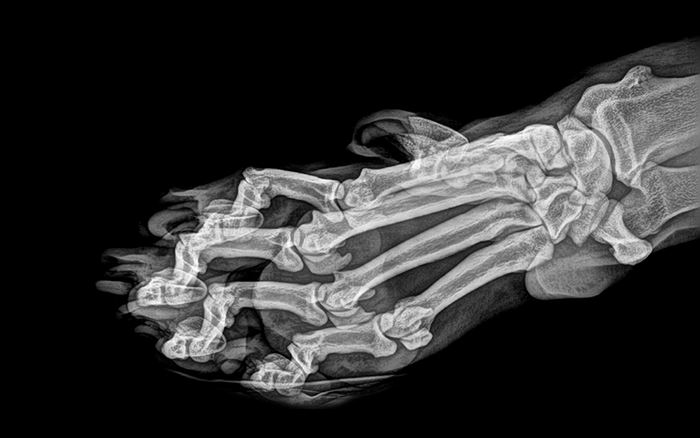

7. กรงเล็บของเสือ (Tiger’s Paw)